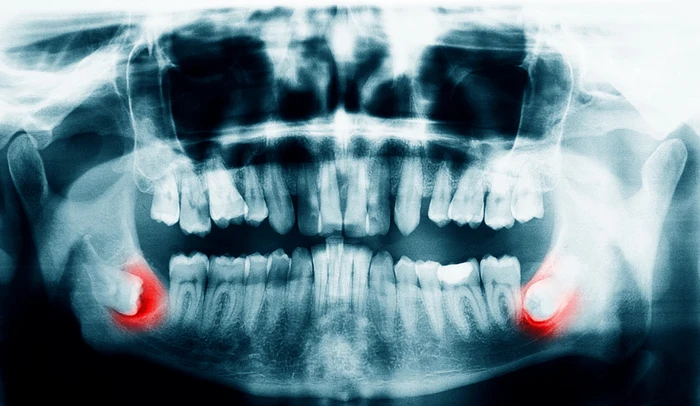

peetunud tarkusehambad

Tarkusehamba eemaldamine

Tarkusehamba väljatõmbamine  on levinud protseduur, mida tehakse juhul, kui hammas ei mahu korralikult suhu, põhjustab valu, põletikku või mõjutab teisi hambaid.